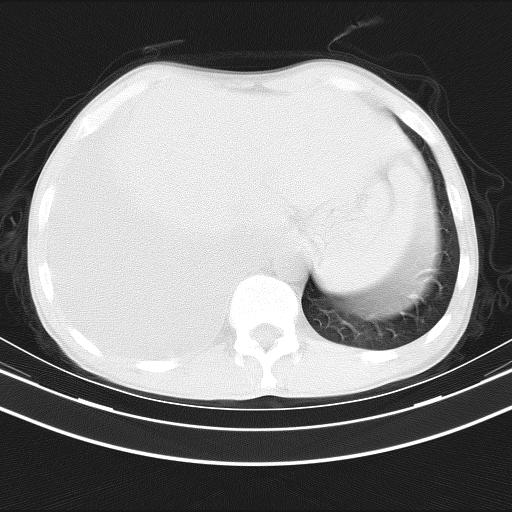

男性,44岁,结核病史多年。现胸闷气短,咳嗽,偶咳血。

1)两肺继发性肺结核伴空洞形成,左肺多发性结核球。2)右侧大量胸腔积液伴右肺部分膨胀不全。3)纵隔淋巴结肿大。

吉大一院胸水抽检结果:结核性胸水

结核性胸水——结核性胸膜炎 感谢楼主反馈结果